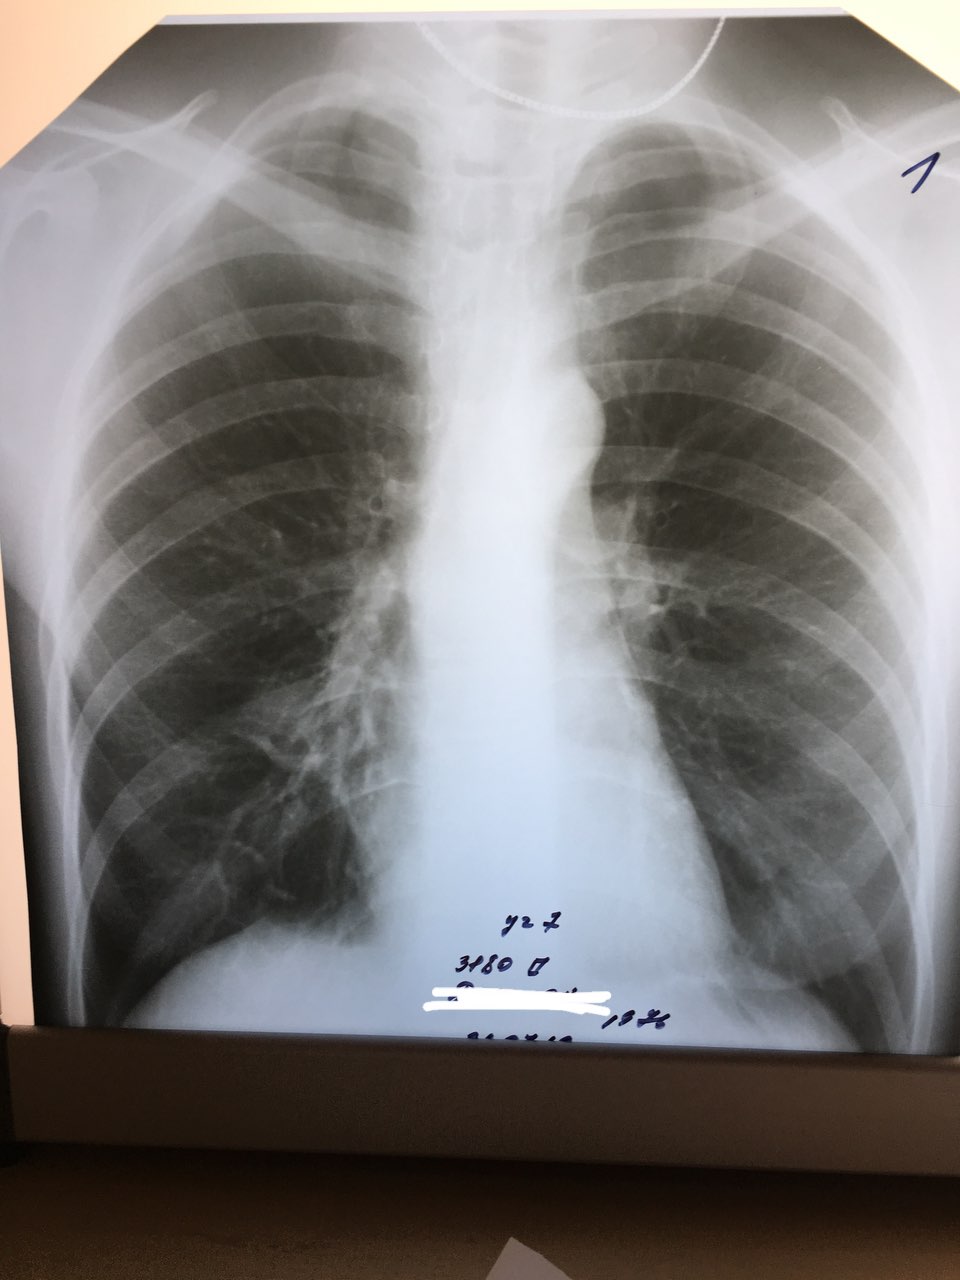

Немного классики

Вич+

Немного интерактива

Женщина?

Значит слева в нижнем поясе инфилтрация ?

И слева   на АV угле кольцевидная тень?

Есть усиления и деформация корня справа

Не-а

Теплее

Бронх слева)

Есть немножко ротации в лева

Javoxir Bahodir o'g'li

Это ателектаз

PEDIATRIC RADIOLOGIST

Интересно ..

Клинику бы знать

PEDIATRIC RADIOLOGIS... in Radiology/Рентгенология Чатоид

Тут скиалогия. Треугольной формы участок затенения, одной стороной сливающийся со срединой тенью, вершиной обращенный к корню.